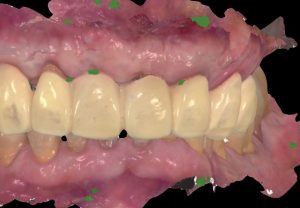

Healing abutments were removed and (b) the second set of temporary restorations was paced. Fig. 17 (i,ii)

Immediate post-operative view of the inserted provisionals. Fig. 19 (i,ii)